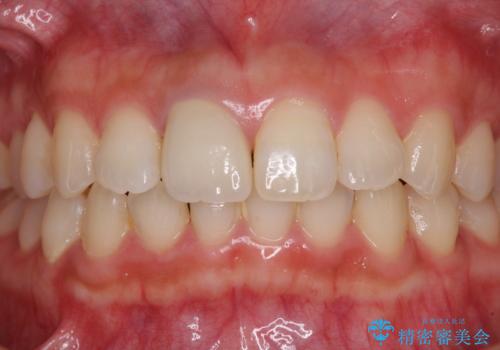

不自然なセラミッククラウンを自然なセラミックに

- 近医にて被せた前歯のクラウンの色の違いを気にして来院された患者様です。

オーダーメイドのオールセラミッククラウンにて補綴することとしました。

元々すきっ歯であったため、隙間を全て埋めると左右で大きさがアンバランスとなることが懸念されました。

違和感のない程度に隙間を小さくして、自然な見た目に仕上げました。